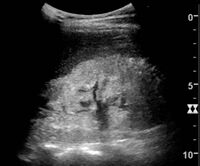

Kidney ultrasonography is useful for diagnostic and prognostic purposes in chronic kidney disease. Whether the underlying pathologic change is glomerular sclerosis, tubular atrophy, interstitial fibrosis, or inflammation, the result is often increased echogenicity of the cortex. The echogenicity of the kidney should be related to the echogenicity of either the liver or the spleen (Figure 22 and Figure 23). Moreover, decreased kidney size and cortical thinning are also often seen and especially when disease progresses (Figure 24 and Figure 25). However, kidney size correlates to height, and short persons tend to have small kidneys; thus, kidney size as the only parameter is not reliable.[54]

End-stage chronic kidney disease with increased echogenicity, homogenous architecture without visible differentiation between parenchyma and renal sinus and reduced kidney size. Measurement of kidney length on the US image is illustrated by '+' and a dashed line.[54]